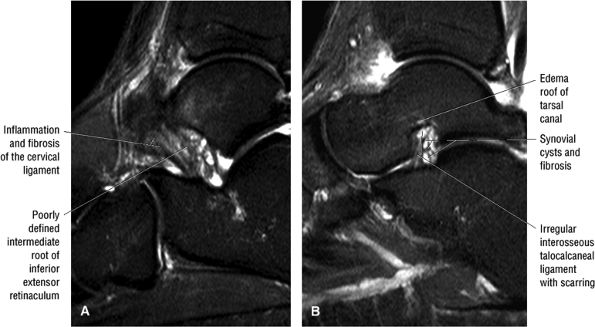

Chronic dysfunction: In spring ligament laxity or rupture, the superomedial calcaneal navicular component is usually injured. The sinus tarsi syndrome may occur after progression from PTT dysfunction to spring ligament pathology. A more detailed discussion of spring ligament pathology can be found later in the chapter.